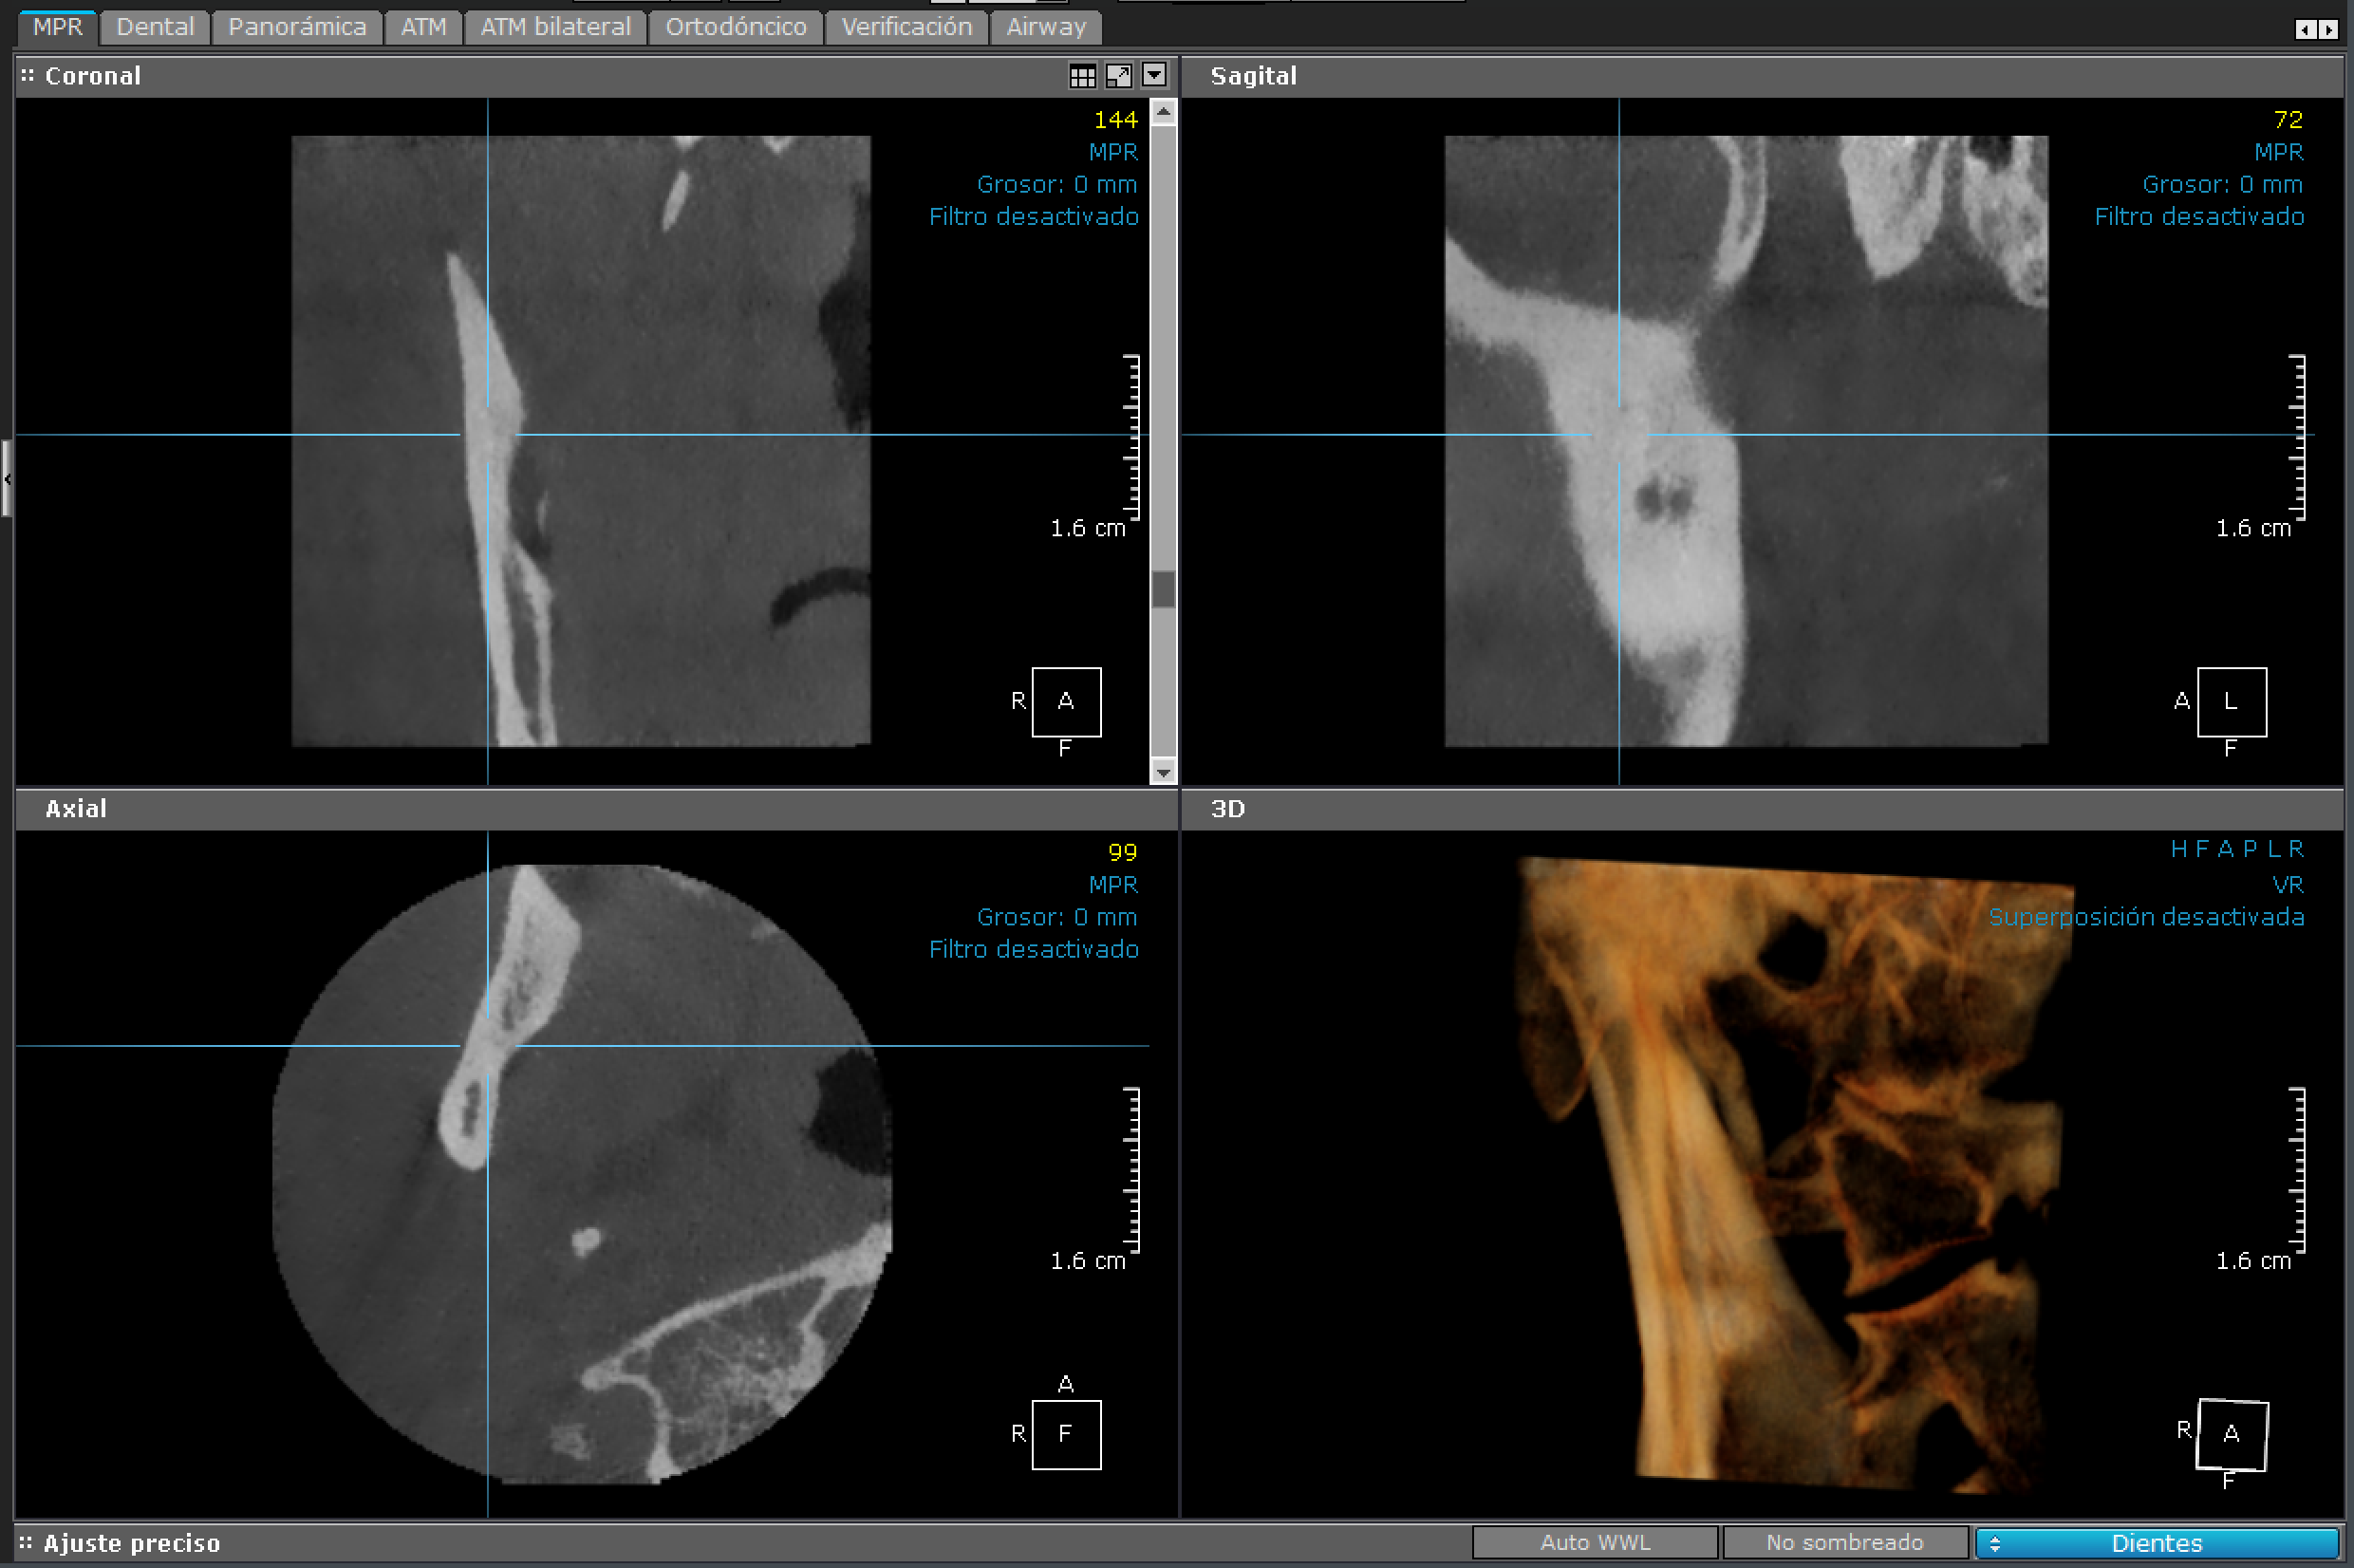

3D - Maxilar Inferior

Maxilar Inferior

Esta imagen está centrada en el maxilar inferior.